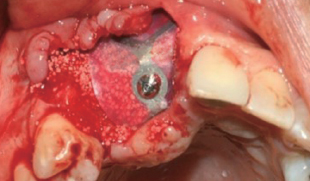

Case 1

수술 전

#45 Implant 식립

#47 Implant 식립

#45 & #46 부위 골 결손

#45 협측 골이식

Wifi-Mesh 준비 및 다듬기

#45 & #46 골 결손 부위에

Wifi-Mesh 위치시킴

#46 발치와 부위에 시행한

Open membrane technique